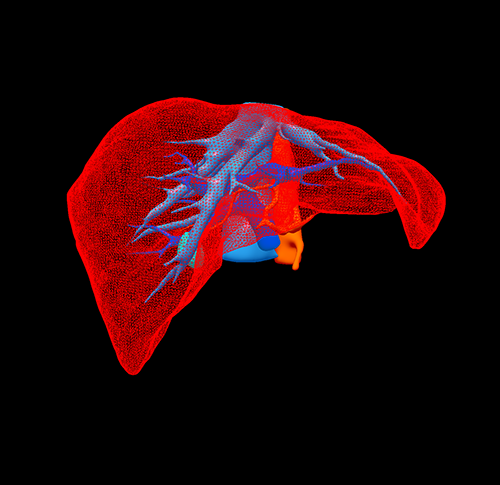

S5 肝癌--腹腔镜S5切除